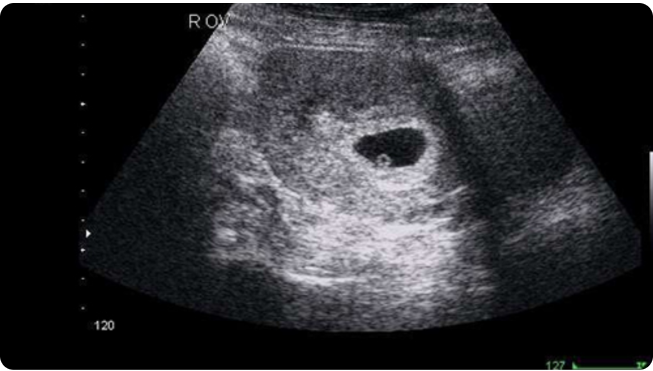

♡29/3/20XX [5 tuần tuổi]

Ba đã đưa Satang đến bệnh viện kiểm tra, em ấy cứ nôn mãi không dứt, chóng mặt suýt ngã nữa, và con biết không, thật khó tin ba nhỏ của con đã mang thai, ẻm giận đến mức nắm lấy cổ áo bác sĩ lôi dậy luôn. Do sao chổi Halley vụt qua Trái Đất nên đàn ông có thể mang thai, cả hai por sốc lắm, cuốn cuồn đi bệnh viện khác khám, vẫn cho kết quả như vậy, tuy có nhiều phân vân nhưng bé con yên tâm, hai por sẽ thương con thiệt nhiều.

(Hình ảnh siêu âm đầu tiên của con, 5 tuần tuổi nhỉ xíu à, nếu bác sĩ không chỉ ba cũng không biết con nằm ở đâu)